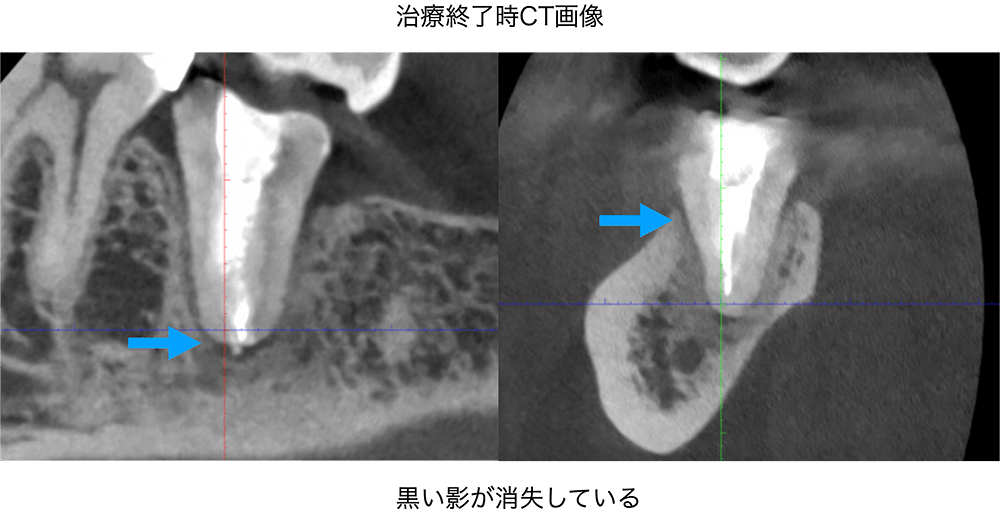

金山デンタルクリニックでは、治療の前に必ずCT撮影を行い、神経の本数や根の形、病変の大きさを正確に診査。治療の可能性や成功率まで含め、CTの画像を見せながら丁寧にご説明しています。治療後の経過もマイクロスコープやCT画像をお見せしながら、ご説明させていただきます。